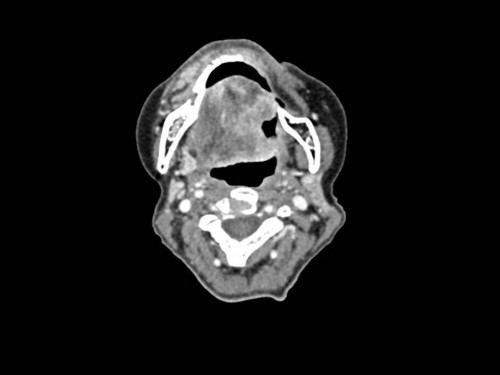

Ältere Frau mit Schleimhautveränderung am linken Zungenrand

Eine 68-jährige Patientin wird zu Ihnen in die MKG-chirurgische Abteilung des Klinikums durch den Hauszahnarzt überwiesen. Jener bemerkte eine Schleimhautveränderung am linken Zungenrand.

Makroskopie - intraoral präoperativ